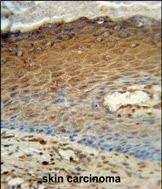

Product Image

- AK7 Antibody (C-term) (Cat. #P30313) immunohistochemistry analysis in formalin fixed and paraffin embedded human skin carcinoma followed by peroxidase conjugation of the secondary antibody and DAB staining. This data demonstrates the use of the AK7 Antibody (C-term) for immunohistochemistry. Clinical relevance has not been evaluated.